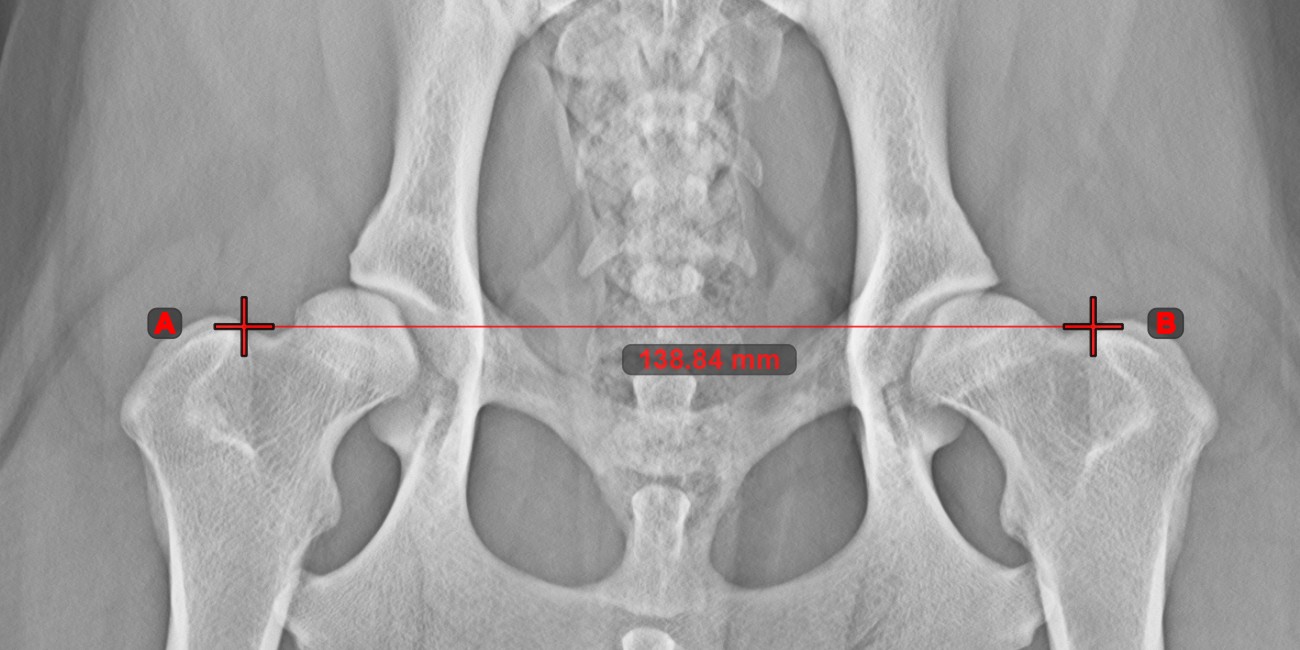

Line Measurement

Create a line measurement to calculate the distance between two points with high precision.

Select the Line Measurement tool and assign it to one of the available mouse buttons. Place the start and end points on the scene or select them from already existing points on the image. The distance between the two points will be automatically calculated by using the default calibration data, or the recalibrated data by the length calibration measurement.

Modify the start and end point by using the Select/Move Item tool. The distance between the two points will be automatically recalculated.